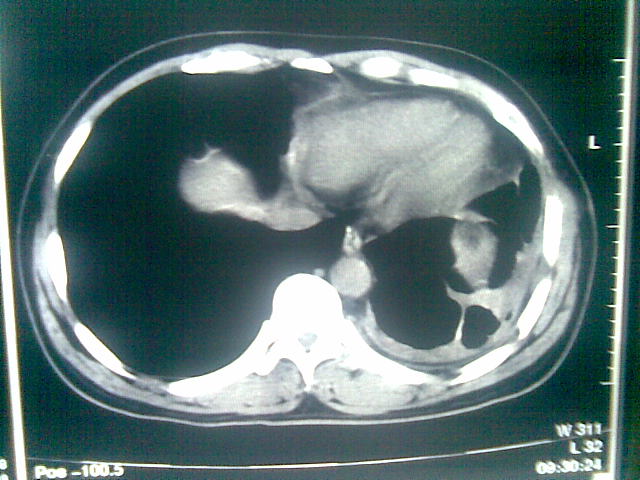

标题: CT23981:男,38岁阑尾炎术后透视胸腔积夜!做CT如下!积液包 [打印本页]

标题: CT23981:男,38岁阑尾炎术后透视胸腔积夜!做CT如下!积液包

可能与阑尾术后关系不太大,1.胸膜增厚粘连见少量气体。包裹脓气胸?左侧网膜囊脓肿?

.胸膜增厚粘连见少量气体。包裹脓气胸

左侧胸膜增厚、粘连+包裹液气胸。